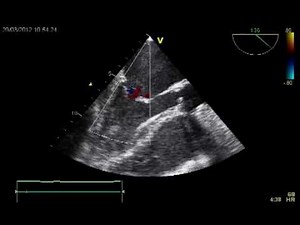

ECHOCARDIOGRAPHY